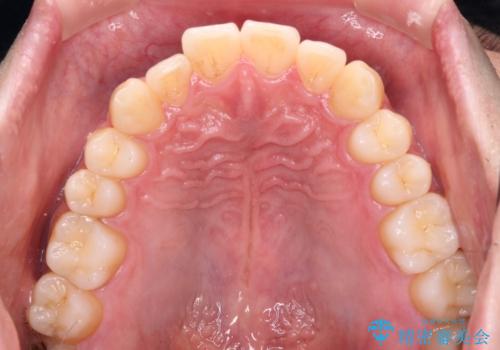

ワイヤー装置での上下前歯の部分矯正

- 上下前歯のデコボコを気にして来院された患者様です。

口元の突出感や奥歯の咬み合わせに問題がなかったため、インビザラインの廉価版パッケージを用いるか上下ワイヤー装置での部分矯正を提案しました。

部分矯正は咬み合わせが不安定になったり、スペースができてしまったりと、適用となる患者様は極めて限られますが、こちらの方はスムーズに治療を終えることができました。